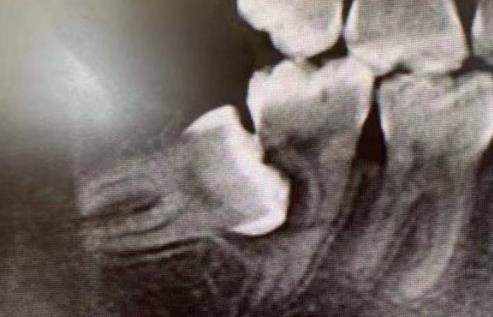

智齒頂壞鄰牙

還有一種就是智齒把旁邊的第七磨牙頂壞了,或者是齲壞嚴(yan) 重需要拔除。而智齒還是完整健康的,就可以牽引過去充當第七磨牙,這樣就不用拔除第七磨牙和智齒兩(liang) 顆牙齒了。